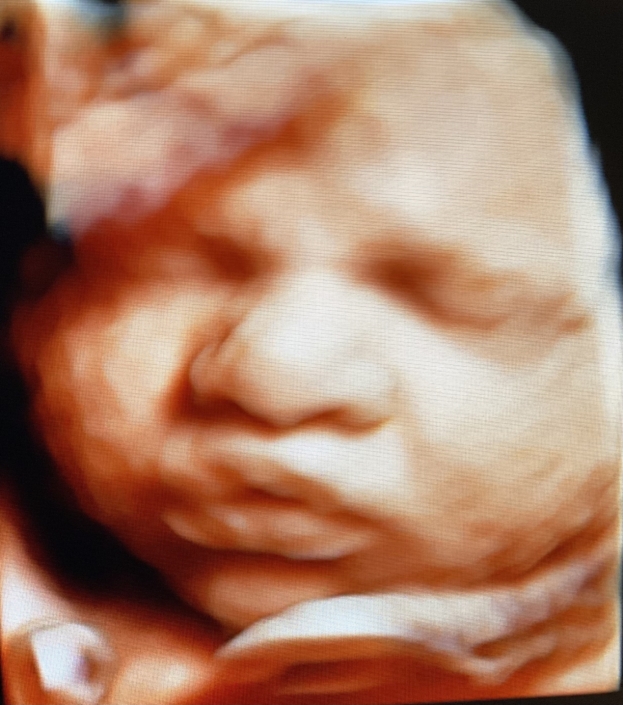

Prenatal Peek®

Prenatal Peek is the leader in 3D 4D Ultrasound. We employ only Certified / Registered Sonographers maintaining unsurpassed standards in 3D ultrasound. You deserve the best! Call us today.